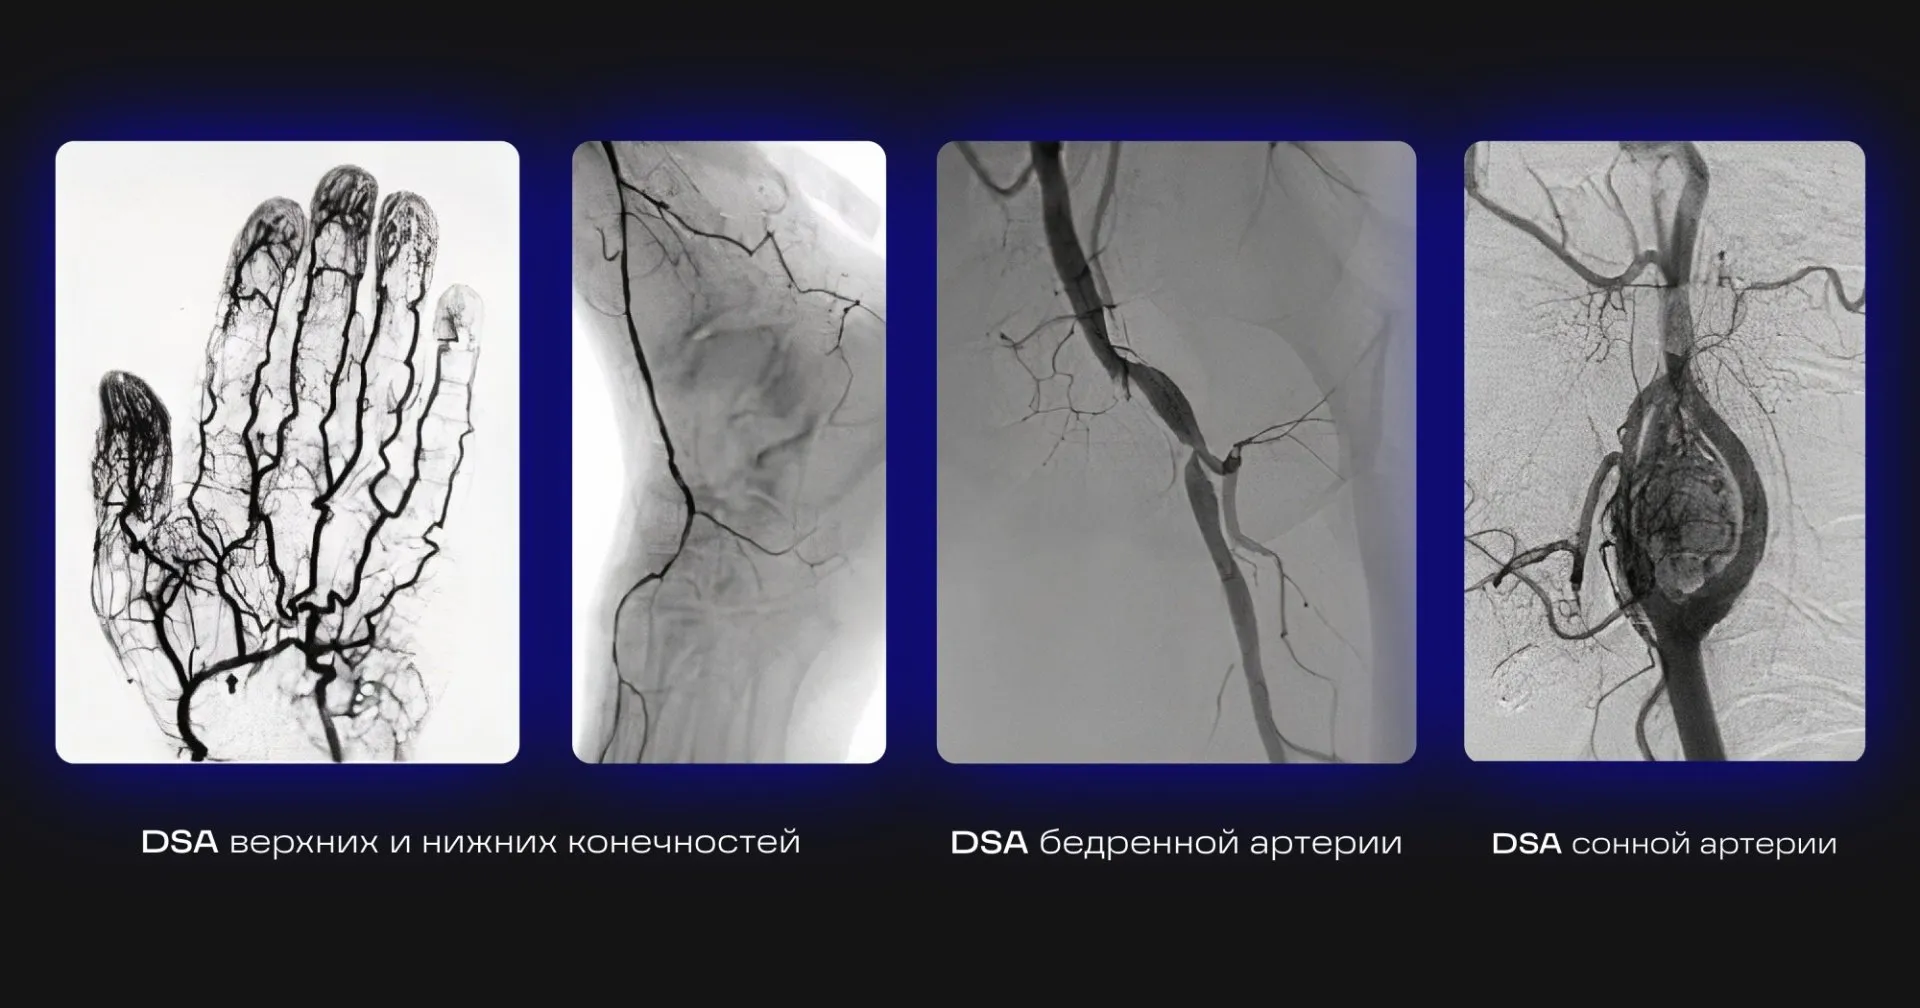

Цифровая субтракционная ангиография (digital subtraction angiography — DSA) — наиболее информативный и точный метод контрастного рентгенологического исследования кровеносных сосудов, дающий возможность детально изучить функциональное состояние сосудов, окольного кровотока, выявить повреждения и протяженность патологического процесса.

Режим пика контрастирования сохраняет в памяти ход болюса контрастного усиления и, при активации этой функции, отображает на кинопетле сосуды с максимальной контрастностью (непрозрачностью).